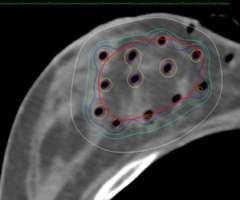

下記に商品説明や配送料・配送方法・注意事項等の説明がございます。b0b13edf-77ad-4cbe-9ee1-。お客様にとって大切な事柄を記載しておりますので、よくお読みいただき、ご了解の上ご購入をお願い致します。Breast cancer: Role of MR-guided radiation therapy。